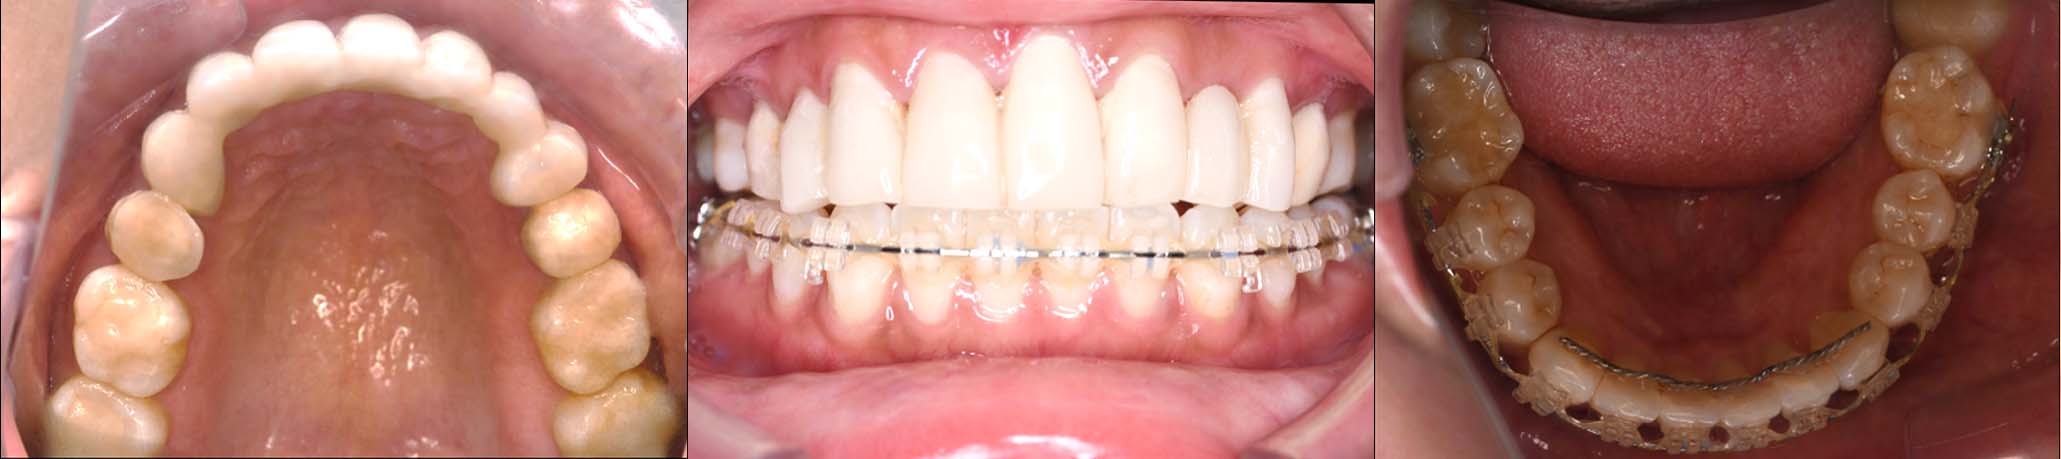

2024年 10月 下顎MTM開始

11月7日

11月28日

12月16日

12月23日